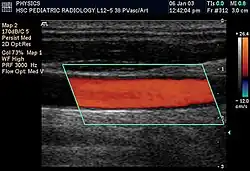

Doppler ultrasonography

Doppler ultrasonography employs the Doppler effect to assess whether structures (usually blood)[58][61] are moving towards or away from the probe, and their relative velocity. By calculating the frequency shift of a particular sample volume, flow in an artery or a jet of blood flow over a heart valve, its speed and direction can be determined and visualized, as an example. Color Doppler is the measurement of velocity by color scale. Color Doppler images are generally combined with gray scale (B-mode) images to display duplex ultrasonography images.[62] Uses include:

- Doppler echocardiography is the use of Doppler ultrasonography to examine the heart.[63] An echocardiogram can, within certain limits, produce accurate assessment of the direction of blood flow and the velocity of blood and cardiac tissue at any arbitrary point using the Doppler effect. Velocity measurements allow assessment of cardiac valve areas and function, abnormal communications between the left and right side of the heart, leaking of blood through the valves (valvular regurgitation), and calculation of the cardiac output and E/A ratio[64] (a measure of diastolic dysfunction). Contrast-enhanced ultrasound using gas-filled microbubble contrast media can be used to improve velocity or other flow-related measurements of interest.